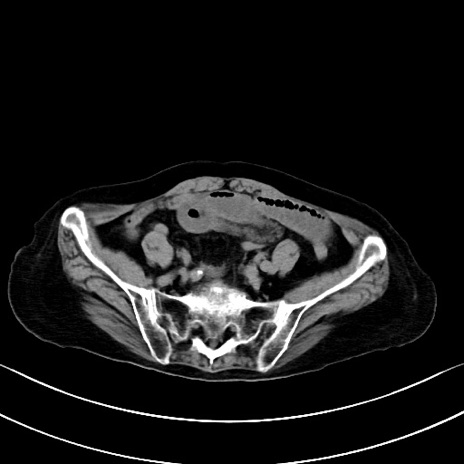

横断像